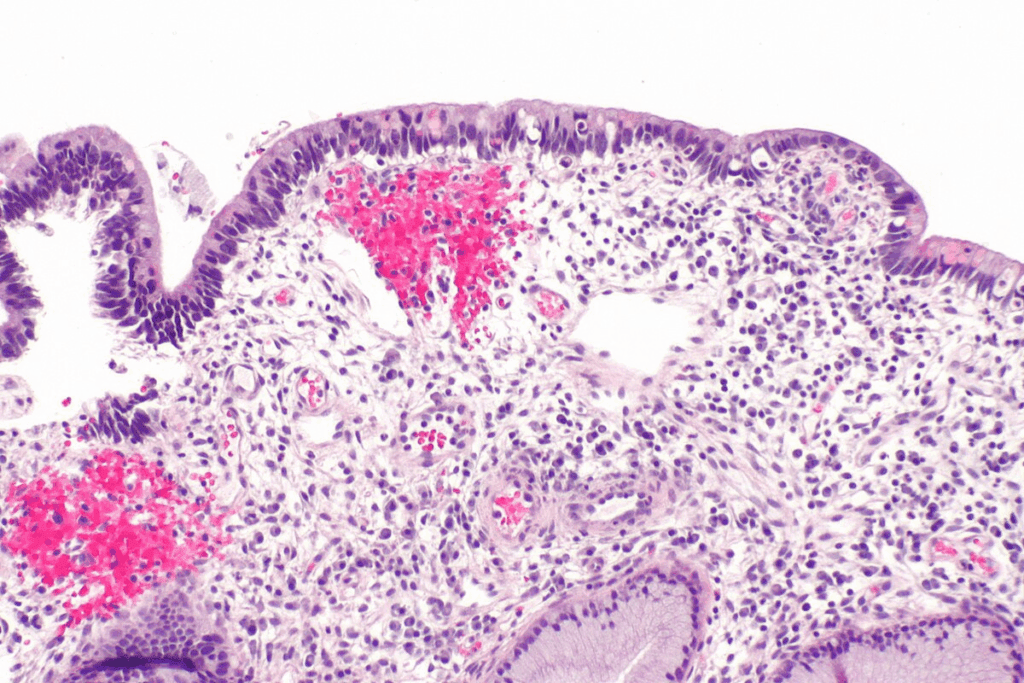

Carcinoma in situ has cancer cells that haven’t crossed the basement membrane. This membrane is a key barrier between cells and tissue. These cells look different from normal cells under a microscope.

Doctors diagnose carcinoma in situ by looking at these cell changes during a biopsy. These changes can range from mild to severe, showing how abnormal the cells are.

Imaging is very important for CIS diagnosis. Mammography is a big help, mainly for ductal carcinoma in situ (DCIS). It spots microcalcifications linked to this condition.

Biopsy is key for a sure CIS diagnosis. The main types are core needle biopsy and surgical biopsy.

Looking at tissues under a microscope is the best way to diagnose CIS. It confirms CIS and tells it apart from invasive cancer.

It checks the cells and how they are arranged. Histological grading and molecular markers give more info on how likely the cancer is to grow.